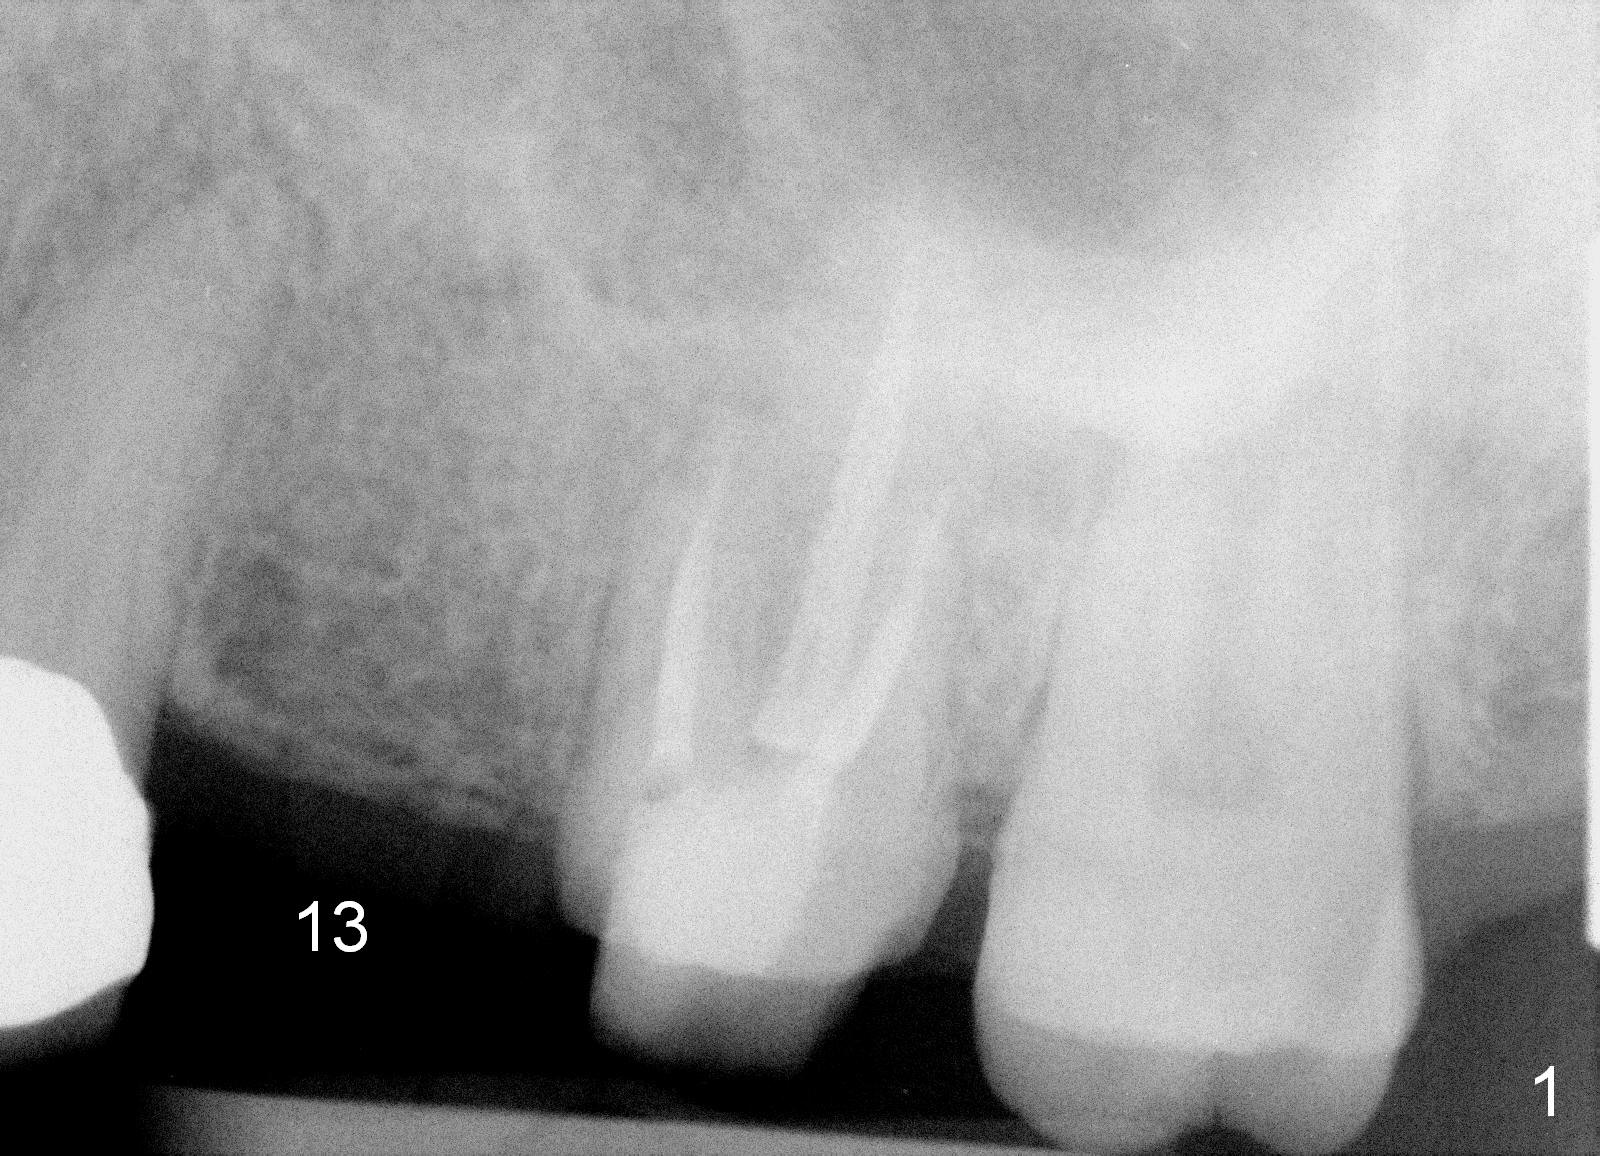

A 45-year-old lady is nervous about dental treatment. The missing tooth #13 was replaced by a 3-unit bridge. The latter is sectioned because the posterior abutment has caries. PA in Fig.1 is taken when root canal therapy and build up are finished. Fig.2 shows the wide edentulous area with a single-unit crown being tried in for #14. Osteotomy is initiated with the crown in place without cementation, since it is easy to determine the mesiodistal position (Fig.3 red lines). Without the crown in place, osteotomy tends to be distal. In this case, the osteotomy is later attempted to be moved distally with Lindamann bur and deepened to 14 mm from the gingival margin (Fig.4). A 2.5 mm reamer is being used at 50 RPM to increase osteotomy with difficulty. Drills have to used at high RPM instead (Fig.5 4x14 mm). A 4.5x14 mm tissue-level implant is placed with insertion torque >60 Ncm (Fig.6 I); a 4x3 mm abutment (A) is placed immediately for an immediate provisional. Fig.7 is taken 7 days postop to show the gingival recipient site formed by the provisional. The patient is so afraid of X-ray that the next one is taken 1.5 years post cementation (Fig.8). It appears that dense bone bundle forms between the crest and the 1st implant thread (adaptation functional change, arrowheads). The bone density continues to increase 2 years 8 months post cementation (Fig.9 *, 10); the bone has grown into the area between the 1st 2 threads (arrow).